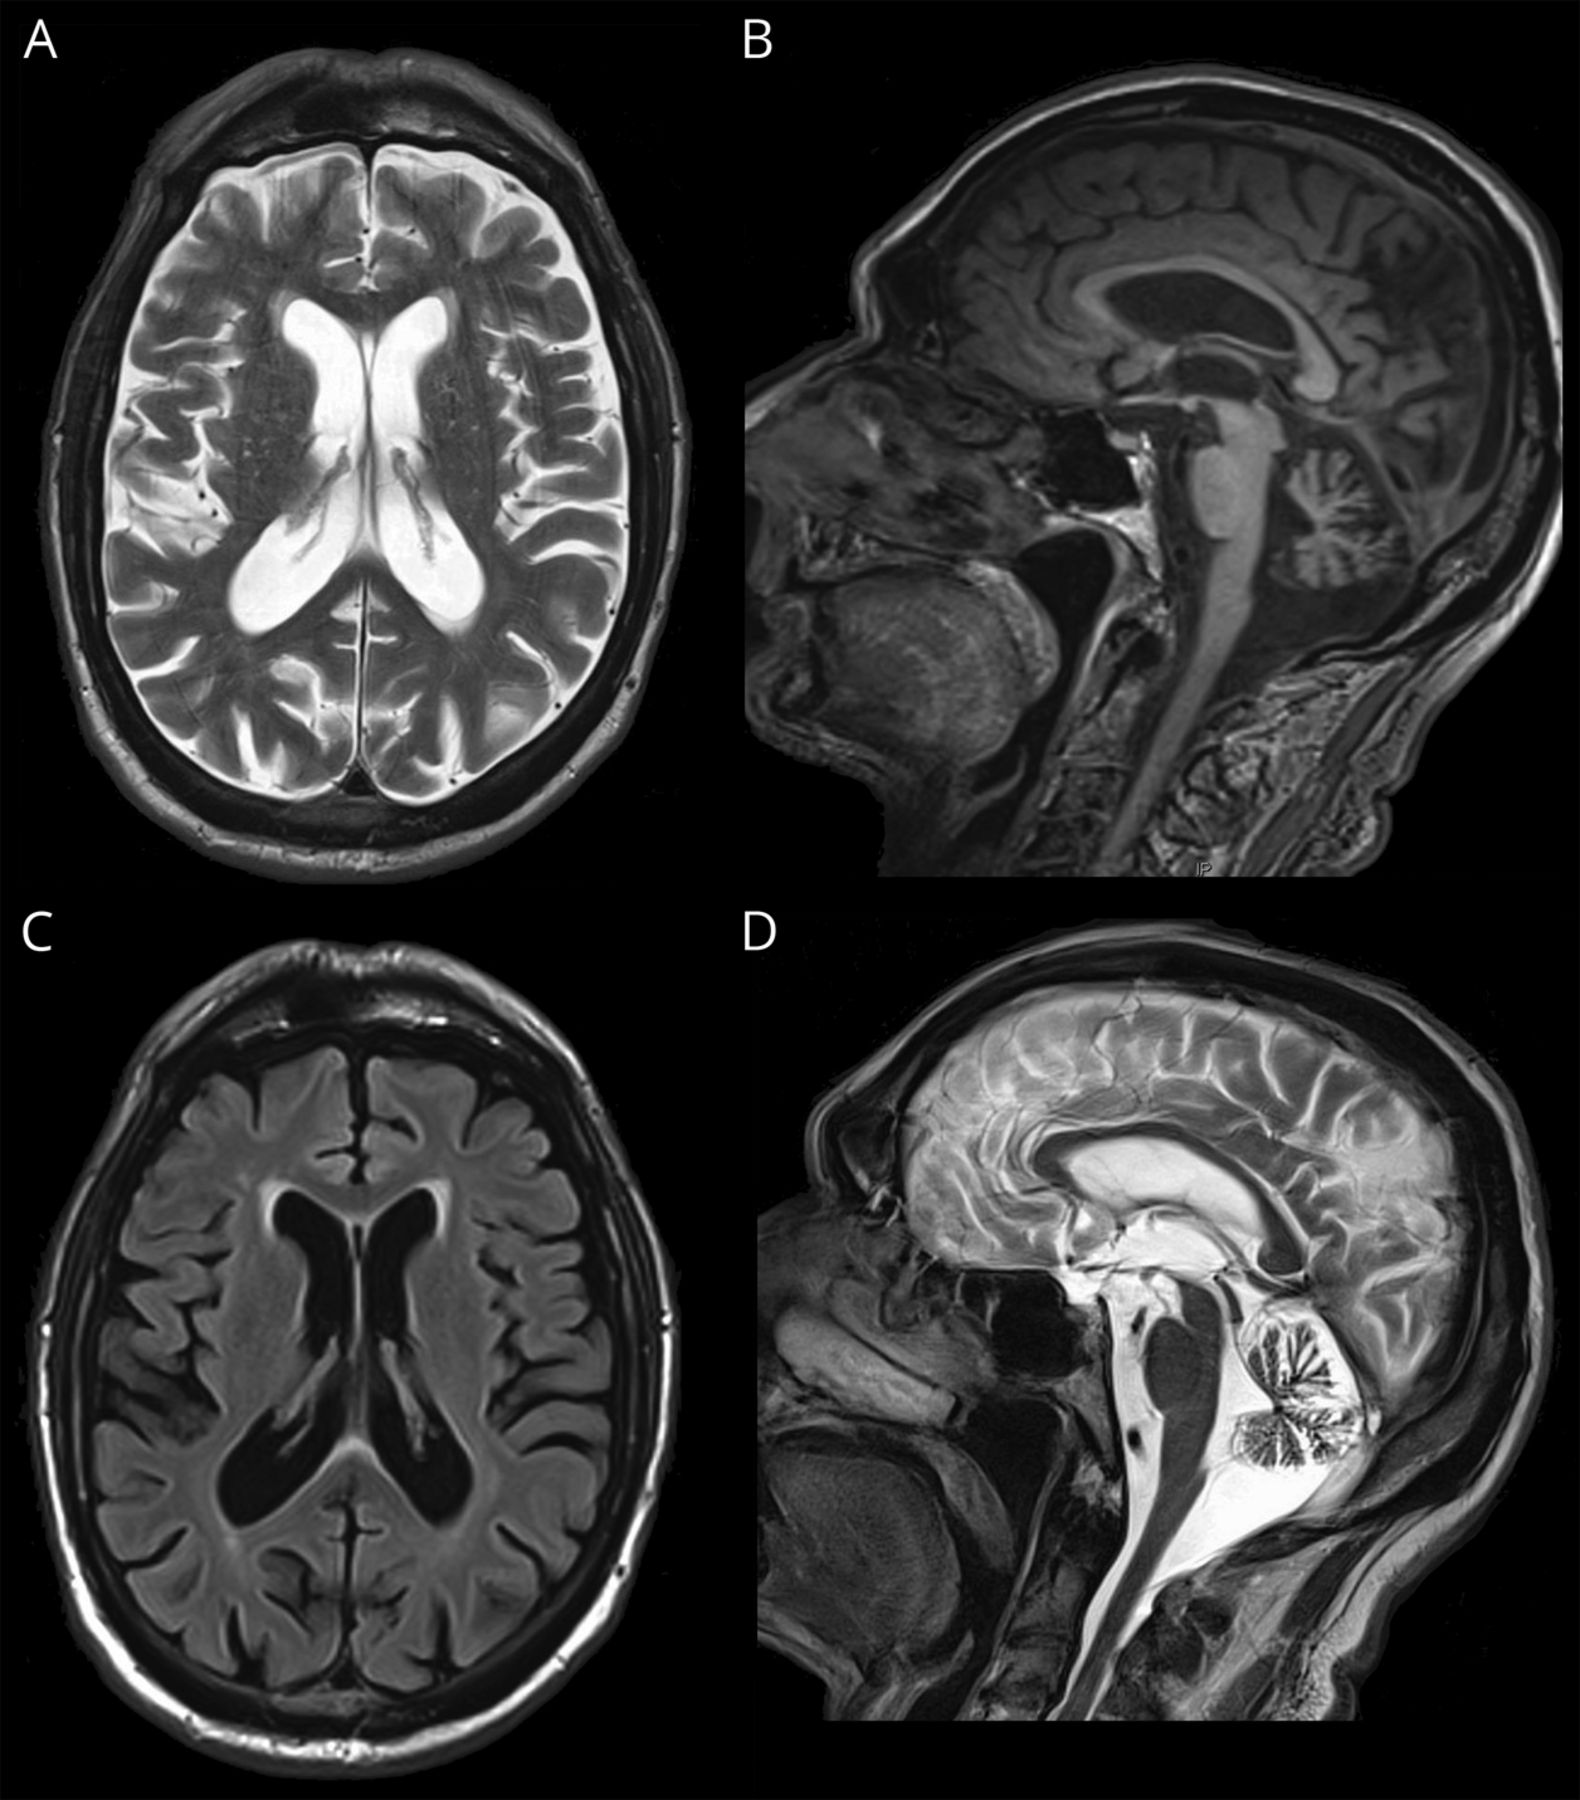

应该根据初步调查发现可逆的医疗问题虽然这些通常会出现亚急性发作。完整的通用药物检查并没有透露任何其他异常。基本的实验室调查包括电解质、全血细胞计数,肝酶,肾功能,甲状腺功能,维生素B12,叶酸是正常的。自身抗体和屏幕antineuronal抗体是正常的。病人有一个正常的艾滋病毒检测和梅毒的屏幕。一个胸部x光是正常的。病人接受了脑成像和1.5 t MRI (T1和T2加权序列包括T2 fluid-attenuated反转恢复),基于neuroradiologic评论显示轻微的皮质和白质脑萎缩(在没有特定的分布)根据全球小脑皮质萎缩评定量表和严重萎缩(图)。

结构1.5 t MRI扫描。(一)t2加权轴节展示全球中央脑萎缩的开沟和轻度脑室扩大。(B) t1矢状切面显示严重小脑萎缩。(C) T2 fluid-attenuated反转恢复轴部分显示轻微的室周的小血管疾病的侧脑室前角附近。(D) t2加权小脑矢状切面显示严重小脑萎缩。